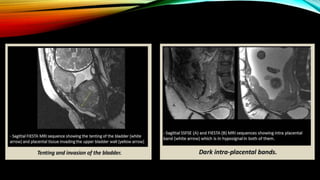

MAGNETIC RESONANCE IMAGING(MRI)

• When to recommend MRI for diagnosis of placenta accreta?

 Equivocal USG findings of abnormal placentation.

 Evaluation of posterior placenta in patients with risk factors.

 Obese patients.

 Complimentary role in specifically delineating the extent of a USG-diagnosed placenta

percreta.